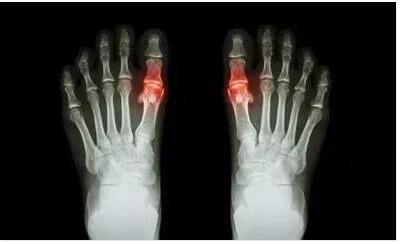

痛风

• 成都风湿医院陈建春 痛风的主要的表现症状是什么

大家知道痛风在生活中很常见,想要更好、更快速的治疗痛风,就必 ...